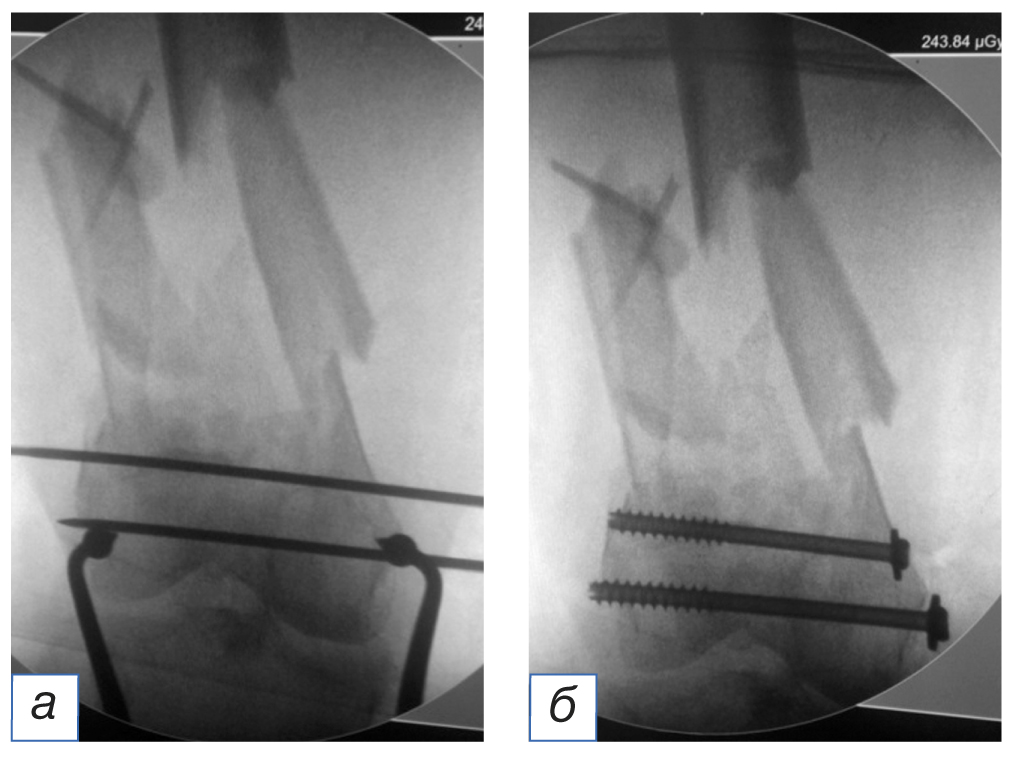

Первым этапом выполняли фиксацию перелома мыщелков стягивающими винтами спереди и сзади от предполагаемой траектории введения штифта после предварительной их репозиции с интраоперационным использованием тазовых щипцов (рис. 4). Из малоинвазивного разреза (до 3 см) сбоку от собственной связки надколенника осуществляли доступ в коленный сустав для проведения направляющей спицы (рис. 5). Затем определяли точку в межмыщелковой ямке, анатомическую ось и траекторию (так называемый угол атаки) для введения ретроградного штифта. Чтобы избежать ятрогенного повреждения крестообразных связок, сначала проводили спицу, ориентируясь на боковом рентгеновском снимке, полученном с помощью электронно-оптического преобразователя, верхнего края линии Blumensaat, а затем выполняли заведение штифта по данной направляющей спице. Все этапы выполнялись под контролем электронно-оптического преобразователя (рис. 6). При правильном введении штифта происходит «саморепозиция» отломков в анатомически правильном отношении, без варусной или вальгусной деформации ДОБК. При необходимости для этого используют поляризующие винты. Дальнейшая хирургическая техника описана в клинических примерах.

Рис. 4. Этапы фиксации перелома мыщелков бедренной кости стягивающими винтами (а, б). / Fig. 4. Stages of fixation of the femoral condyles fracture with cannulated screws (а, б).